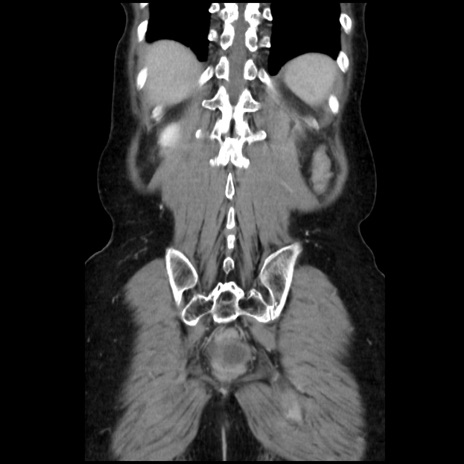

症例32(冠状断像)

【症例】40歳代 女性

【主訴】上腹部痛、嘔気・嘔吐

【現病歴】約9時間前頃から急に上腹部痛、嘔気、嘔吐が出現。改善しないため救急要請。

【既往歴】子宮頚癌(広汎子宮全摘術、放射線療法)、腸閉塞

【身体所見】腹部:平坦、軟、腸雑音亢進、上腹部を中心に腹部全体に圧痛あり。

【データ】WBC 8400、CRP 0.03